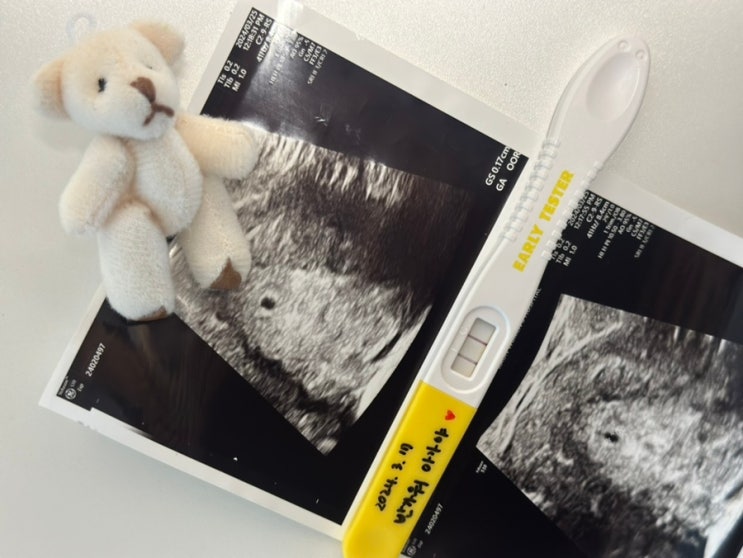

작고 소중한 생명체를 만나다. 초보엄마 임신기록 시작합니다. Hello baby 1.

A good memory 좋은 추억 쌓기 저에게 소중한 생명체가 찾아왔습니다. 반가워 아가야? 2024.03.17 #임...